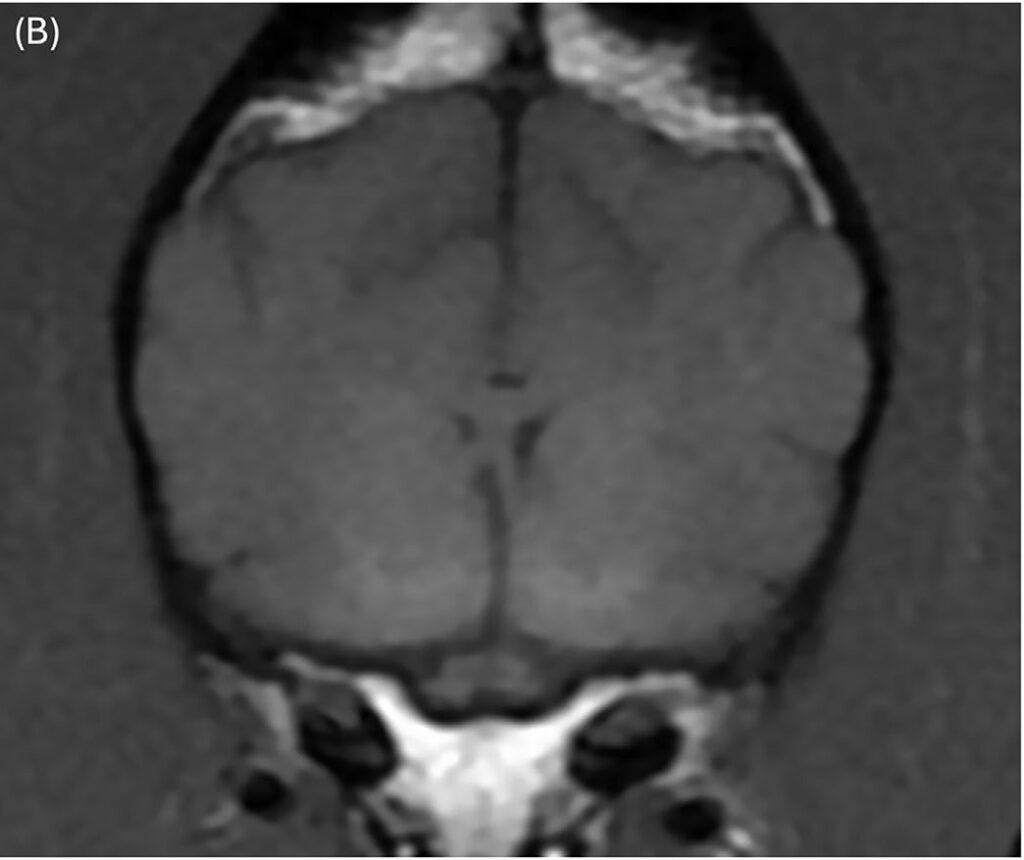

颈椎MRI图像大多未见异常,仅显示颈椎间盘纤维环的轻度非压迫性突出。脑部成像显示双侧对称、边界不清的T2和T2-FLAIR高信号,影响丘脑(图1A)、内侧和外侧膝状体(图2A)、导水管周围灰质和红核(图2A)。在双侧豆状核(图3A)、丘脑(图1B)和膝状核(图2B)内可见T1高信号。这些病变未显示对比增强。未在任何可见的骨或软组织结构中发现异常。

图1. 丘脑核(白色箭头)中可见双侧对称、边界不清的T2(A)和T1(B)高信号。

与治疗前相比,先前注意到的T2和T2-FLAIR高信号区域都有显著改善。在丘脑(图4C)、内侧和外侧膝状体以及红核中仅见非常轻微的双侧对称、边界不清的T2高信号(图5C)。先前注意到的豆状核中的T1高信号区域已完全消失(图6B)。

图4.(C)铜螯合治疗开始7个月后,丘脑核的T2高信号明显改善。

本病例中,3岁斑点狗的诊断基于MRI发现和肝脏活检中铜相关肝病的存在。MRI显示双侧对称的T2和T2-FLAIR高信号,主要影响丘脑、内侧和外侧膝状体、红核,以及双侧T1高信号的豆状核和丘脑,提示潜在的代谢功能障碍。肝脏活检显示严重的铜相关肝炎,铜含量显著升高,支持威尔逊病的诊断。铜螯合治疗后,临床症状和MRI改变均显著改善。